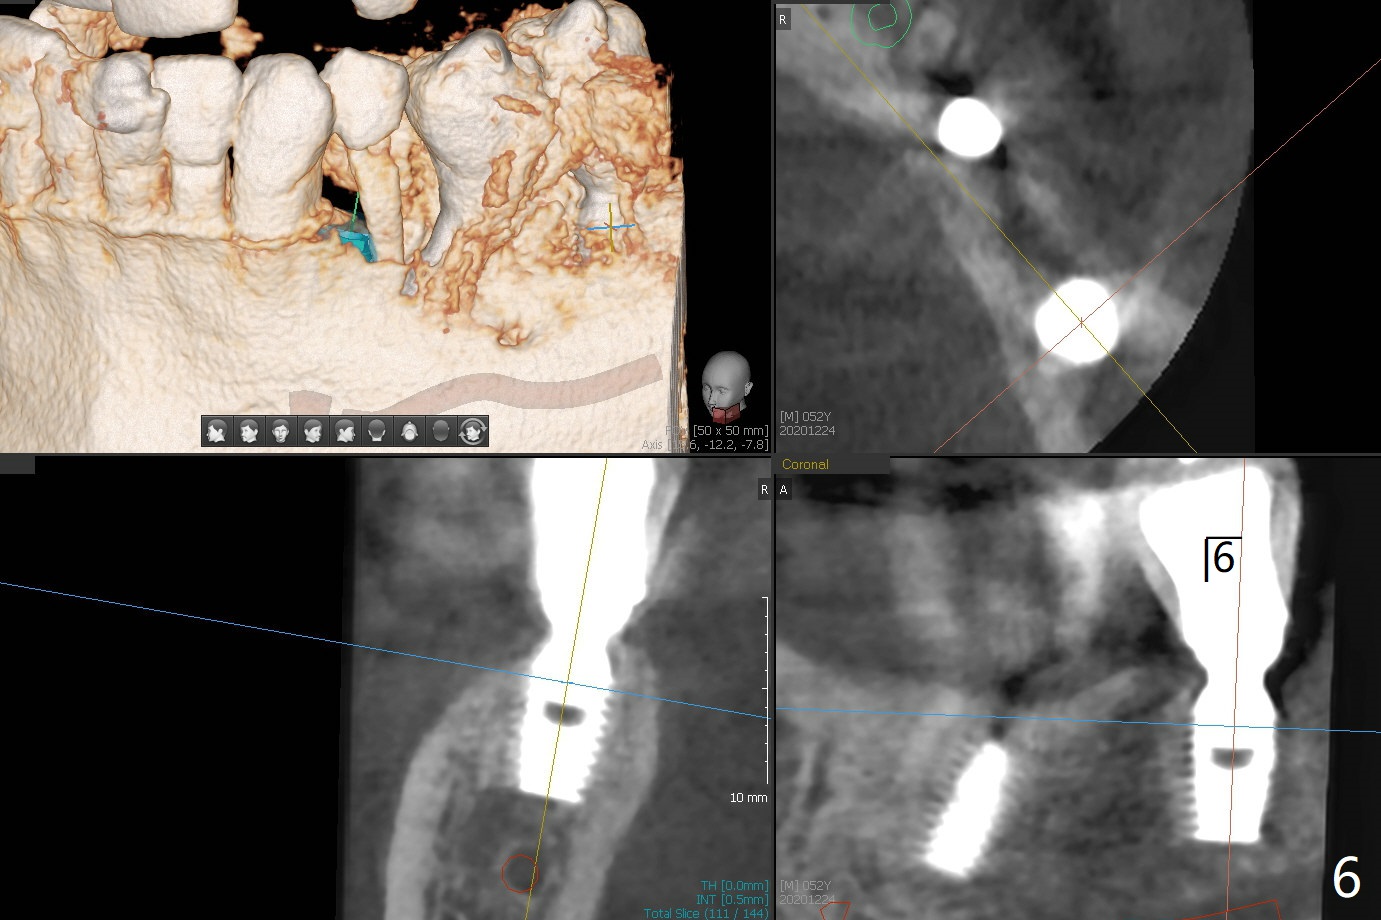

52岁男右下4植体脱落,植骨后,使用左侧咀嚼,发现左下4松动(图一,二),无法吃饭,认为必须拔除植牙(图三,四),徒手种植的邻近植体位置不好,但无骨质吸收(图五,六(牙冠粘固后9年10月)),4种植必须用导板